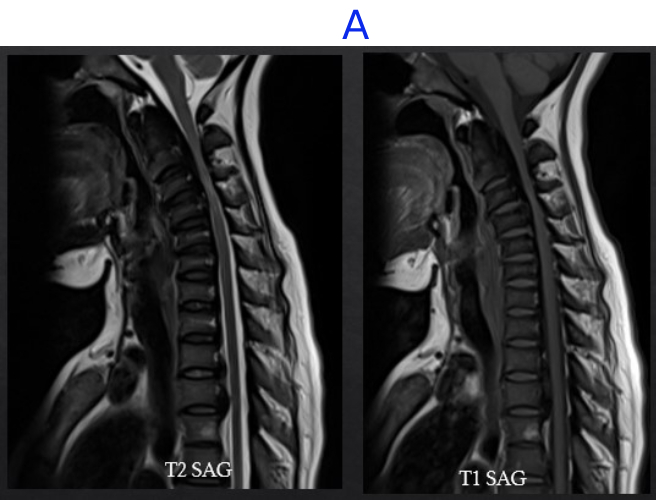

A) LEGENDS

• Vertebral Body and endplate of various vertebrae appear diffusely hypointense on T1 and T2 sequences .

• Compression and narrowing of the cervical canal with spinal cord hyperintensity at the level of C3 and C4 vertebrae– suggestive of myelo-malacia.